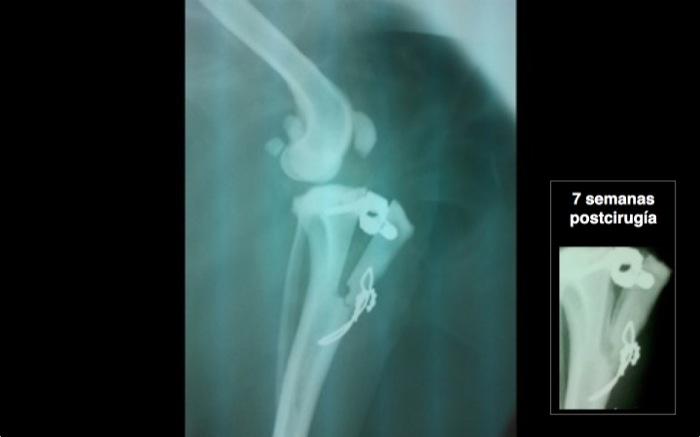

La imagen anteroposterior presenta la banda en ocho y la cesta que está alejada de la superficie articular. El cerclaje según el peso va de 0,8 a 1,2 mm y a este perro de 9,600 kg le corresponde 0,8 ó 1 mm. En este caso se ha utilizado 0,8 mm.

La imagen postquirúrgica es la que se espera salvo que se comprueba una grieta al final de la osteotomía. No era visible en la operación porque quedaba bajo el periostio y no debe influir pero refuerza la opción de poner siempre un cerclaje. Esta técnica es más sencilla sin perder seguridad respecto a las otras que modifican la biomecánica de la rodilla y persiguen una estabilidad dinámica alterando la geometría de la rodilla. Otras opciones que eliminan la función del LCC son: TPLO 1993 tibial plateau levelling osteotomy, TTO triple tibial osteotomy, TTA 2002, tibial tuberositty advancement y la primera de 1984 con la TWO, tibial wedge osteotomy.

Entre 4 a 12 semanas se encuentra el tiempo de curación. En esta imagen tomada a las 7 semanas el desplazamiento es fluido en los paseos aunque aún se resiente con una actividad excesiva cuando salta o estira nervioso enfrentándose a otros perros. Se insiste de nuevo en la actividad moderada hasta la octava semana aunque el pronóstico a estas alturas lleva buen camino.